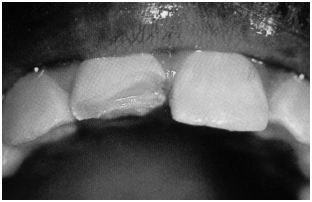

Fractures of the Crown. Crown fractures may be divided into uncomplicated and complicated categories. Uncomplicated crown fractures involve the enamel or enamel and dentin. (See Figure 1.)

Crown fractures through the enamel usually are not sensitive to forced air, hot or cold, or percussion and usually pose no threat to the dental pulp. Immediate treatment in the ED is not necessary but may consist of smoothing the sharp edges off the tooth with an emery board or small hand-held disc sander. It is very important to reassure the patient that a dentist can restore the tooth to its natural appearance using composite resins and bonding materials. Follow-up is important, as pulp necrosis rarely can occur as can color change (0-3%).2,18 (See Figures 1 and 2.)